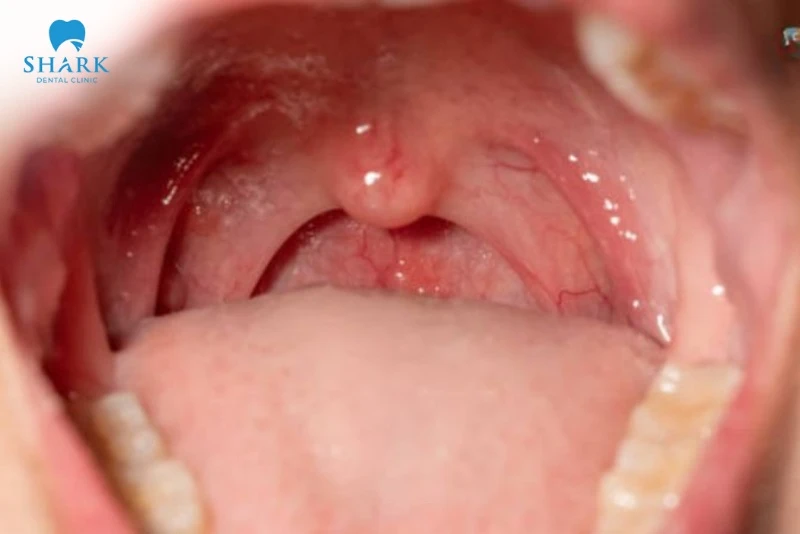

Amidan

Là hai khối mô lympho nằm hai bên thành họng.

- Trạng thái bình thường: Amidan có màu hồng tương đồng với niêm mạc họng, bề mặt nhẵn hoặc hơi gồ ghề tự nhiên nhưng không sưng to, không có hốc mủ trắng.

- Chức năng: Hoạt động như “người lính gác cổng”, sản sinh kháng thể để bắt giữ và tiêu diệt vi khuẩn xâm nhập.

Dấu hiệu và hình ảnh vòm họng bình thường

Việc quan sát hình ảnh vòm họng bình thường thực tế sẽ dựa trên các tiêu chí cụ thể về màu sắc, niêm mạc và cảm giác thực thể.

- Màu sắc chuẩn: Toàn bộ vùng họng, lưỡi gà và amidan có màu hồng nhạt, không xuất hiện các vùng đỏ rực hoặc tím tái.

- Sự đồng nhất: Màu sắc trải đều từ vòm miệng xuống phía sau thành họng.

- Độ sạch: Bề mặt sạch sẽ, không có đờm nhớt đặc quánh, không có các đốm trắng đục hay vết loét.